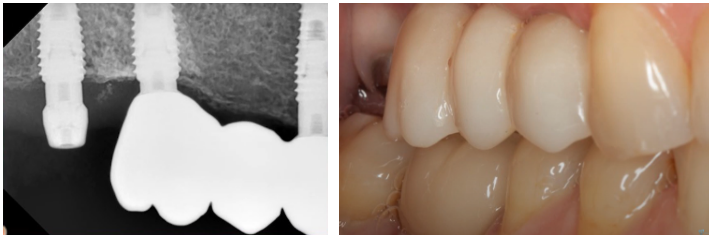

The bridge was temporarily removed; the gingival condition around all implants was excellent. The decision was made to proceed with a single, screw-retained restoration for the third implant and to remake the bridge to include all three units.

Checking the condition of soft tissues before installing a bridge and single-tooth restoration. YouTube/ Implantarium/ Rauf Aliyev

After removing the temporary bridge, a scan body was placed on the final implant. Based on the digital impression, a single zirconia crown was fabricated on a tall titanium base. The single-unit restoration was also torqued to 35 Ncm, which served as the final confirmation of its stability.

The images below show the final three-unit restoration as of September 2020.

Final restoration: bridge and single restoration installed in September 2020. Youtube/ Implantarium/ Rauf Aliyev

The patient returned for a follow-up examination one year later, in September 2021. The gingiva was healthy, with no signs of recession or inflammation.

A photo of the restoration one year after the final version was installed – a bridge + single crown: the soft tissues are healthy. YouTube/ Implantarium/ Rauf Aliyev

The follow-up radiograph also showed that everything was all right. The bone tissue around the implants was even in better condition after a year.

Control radiograph 12 months after restoring the previously mobile implant. YouTube/ Implantarium/ Rauf Aliyev

This is a standard outcome in such situations. In the absence of complications like inflammation or radiographic signs of pathology, the implant fully re-integrates and can provide service for decades.